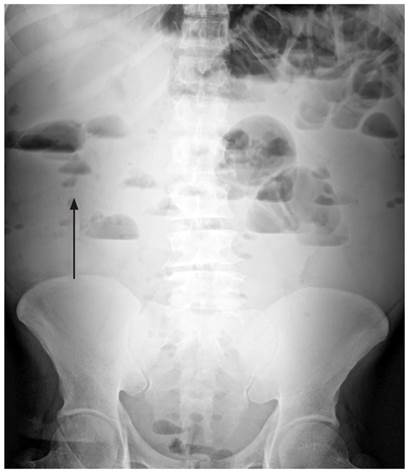

Se inició el manejo con líquidos intravenosos (y se logró normalidad hemodinámica) y cubrimiento antibiótico a base de ampicilina/sulbactam. Se solicitaron estudios paraclínicos que mostraron un hemograma con leucocitos: 15 530/μL, hemoglobina: 10,4 g/dL y plaquetas: 130 000/μL, además de proteína C-reactiva (PCR): 114 mg/dL, gases arteriales con pH: 7,31, presión parcial de dióxido de carbono (pCO2): 22,7 mm Hg, presión parcial de oxígeno (PO2): 70,3 mm Hg, bicarbonato (HCO3): 11,2 mmol/L y base exceso (BE): -12,7 mmol/L. Se realizaron radiografías de tórax de pie (Figura 1) y de abdomen simple (Figura 2).

Figura 1 Radiografía de tórax posteroanterior de pie. Se aprecia la imagen del neumoperitoneo bilateral (flecha) con colección subpulmonar basal bilateral con nivel hidroaéreo en la base izquierda acompañado de la elevación de ambos hemidiafragmas y opacidades intersticiales reticulares biliares bilaterales, sin derrames pleurales.